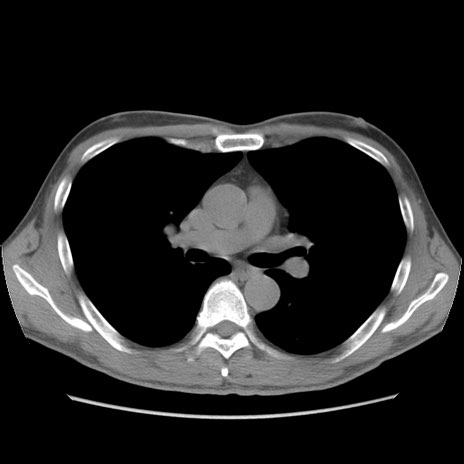

症例56 CT(横断像)

脂肪ウインドウ